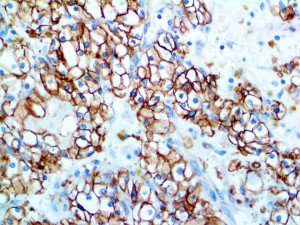

It is the ICU physician who is most likely to witness one of the deadliest manifestations of the abnormal immunological response, the cytokine storm syndrome (CSS). This response is also referred to by some as the cytokine release syndrome (CRS). CSS is characterized by continuous activation and expansion of macrophage and lymphocyte populations, which secrete large amounts of cytokines, causing the cytokine storm. This massive cytokine release is akin to hemophagocytic lymphohistiocytosis (HLH) disease, a syndrome characterized by initial unchecked and persistent activation of cytotoxic T lymphocytes and NK cells.

Clinical and laboratory manifestations of HLH include fever, enlarged liver and/or spleen, neurologic dysfunction, coagulopathy, liver dysfunction, cytopenias (i.e., low levels of erythrocytes, leukocytes, and/or platelets), hypertriglyceridemia, hyperferritinemia, hemophagocytosis, and eventually diminished NK cell activity as the immune system becomes progressively paralyzed. HLH can be familial (primary HLH) or secondary to another disease process (sHLH), such as rheumatic disease, in which it is referred to as macrophage activation syndrome (MAS, characterized by elevated ferritin).